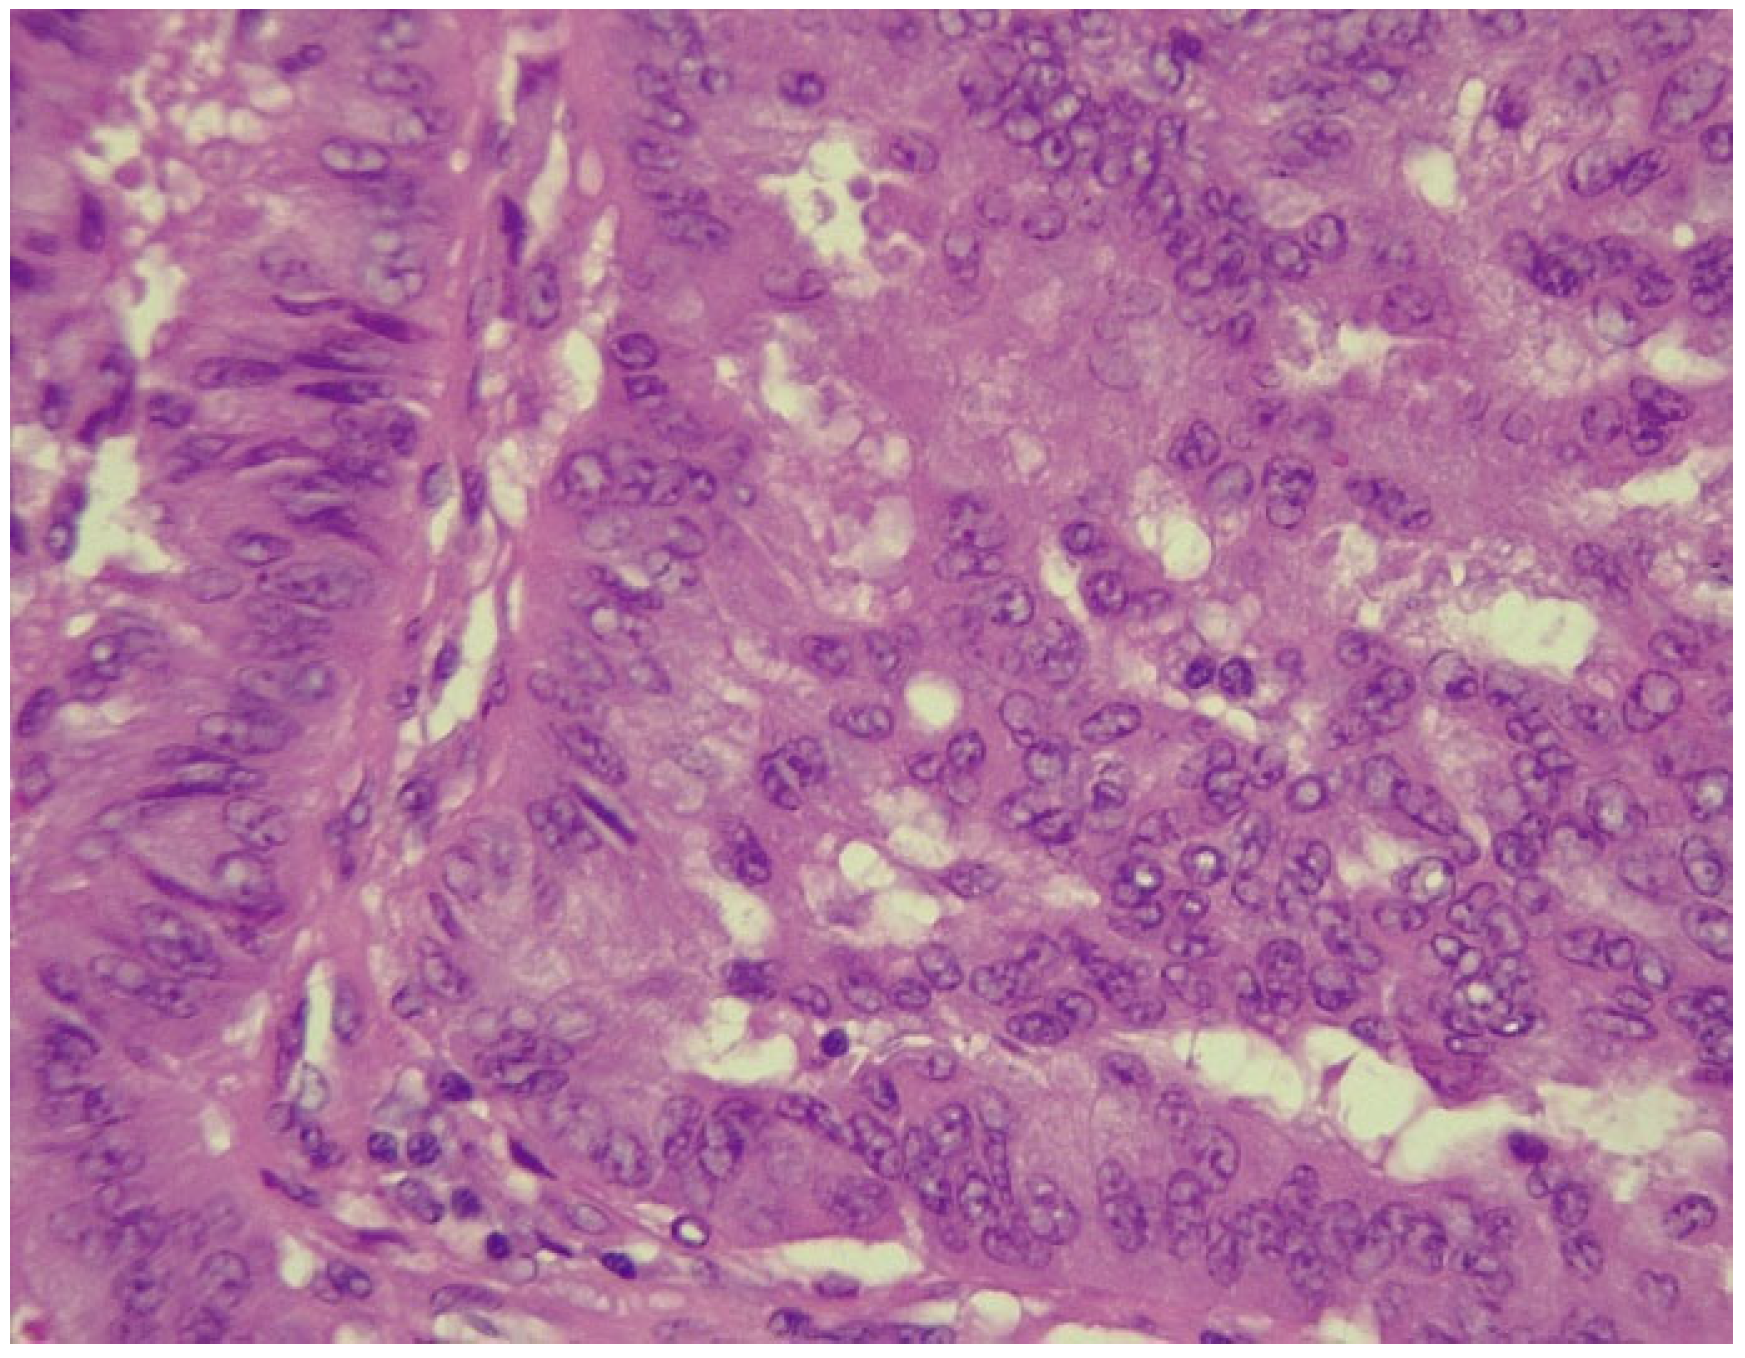

However, after CT-guided biopsy performed on 28 June 2024 and consecutive pathological sample examination, the suspicion of lymphoma was completely dismissed. The tissue sample analysis consisted of usual hematoxylin-eosin (HE) staining and immunohistochemistry (IHC). As depicted in Figure 6 and Figure 7, the optical microscopy examination of the tissue revealed aspects consistent with the diagnosis of a non-small cell lung carcinoma (NSCLC). The main microscopic description was of a non-mucinous type of lung adenocarcinoma.

Figure 6.

NSCLC showing tumor cells with marked pleomorphism and enlarged hyperchromatic nuclei (HE stained section, photographed using Leica DM750 microscope (Leica Microsystems, Heerbrugg, Switzerland) with digital camera objective at ×400 magnification).